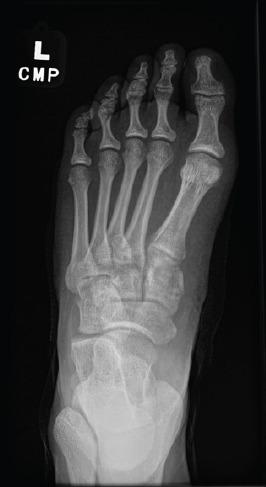

Various methods are used for open reduction and internal fixation of Lisfranc injuries, and each shows different post-treatment outcomes. Other than the common post-surgery problems in these patients, including possible non-anatomical reduction, implant loosening, breakage, and arthritis, most of these patients will undergo a second surgery for implant removal which itself might cause further complications. To reduce the need for re-operation, bio-degradable or bio-integrative implants can be promising; however, the short- and long-term outcomes have been scarcely investigated to date.

We followed up 10 adult patients who received bio-integrative screws for Lisfranc injuries. The patients were asked to fill out the patient-reported outcome measures (PROMs) surveys during one of the follow-up visits. We gathered variables including the type of injury, pain score, and PROMs including physical function (PF), pain interference, pain intensity, and depression. We evaluated the patients for wound dehiscence, non-union, and hardware failure. The median (interquartile range [IQR]) follow-up time of the patients in this study was 9 (4-11.5) months. Nine out of 10 patients with Lisfranc injuries who received bio-integrative screws showed improvements in their pain scores and started progressive weight-bearing. Among 3 patients who had sport-related Lisfranc injuries, 2 returned to play in <6 months, and one started side-to-side agility work in <3 months. The median (IQR) scores of PROMs representing PF, depression, physical health, mental health, pain interference, and pain intensity were 49.5 (30.1-61.9), 41 (41-49), 50.8 (39.2-57.7), 59 (48.9-63.7), 51.7 (41.6-72.6), and 43.5 (37.8-55.2), respectively.

多种方法用于Lisfranc损伤的切开复位内固定,每种方法都显示出不同的治疗后结果。除了这些患者常见的术后问题,包括可能的非解剖复位、植入物松动、断裂和关节炎外,这些患者中的大多数将接受二次手术取出植入物,而这本身可能会导致进一步的并发症。为了减少再次手术的需求,生物可降解或生物整合植入物可能很有前景;然而,迄今为止,对其短期和长期结果的研究很少。

我们对10例接受生物整合螺钉治疗Lisfranc损伤的成年患者进行了随访。要求患者在一次随访中填写患者报告的结局指标(PROMs)调查问卷。我们收集了包括损伤类型、疼痛评分以及PROMs(包括身体功能(PF)、疼痛干扰、疼痛强度和抑郁)等变量。我们评估了患者的伤口裂开、骨不连和内固定失败情况。本研究中患者的中位(四分位间距[IQR])随访时间为9(4 - 11.5)个月。10例接受生物整合螺钉治疗的Lisfranc损伤患者中有9例疼痛评分有所改善,并开始逐步负重。在3例与运动相关的Lisfranc损伤患者中,2例在6个月内恢复运动,1例在3个月内开始进行双侧敏捷性训练。代表PF、抑郁、身体健康、心理健康、疼痛干扰和疼痛强度的PROMs中位(IQR)评分分别为49.5(30.1 - 61.9)、41(41 - 49)、50.8(39.2 - 57.7)、59(48.9 - 63.7)、51.7(41.6 - 72.6)和43.5(37.8 - 55.2)。